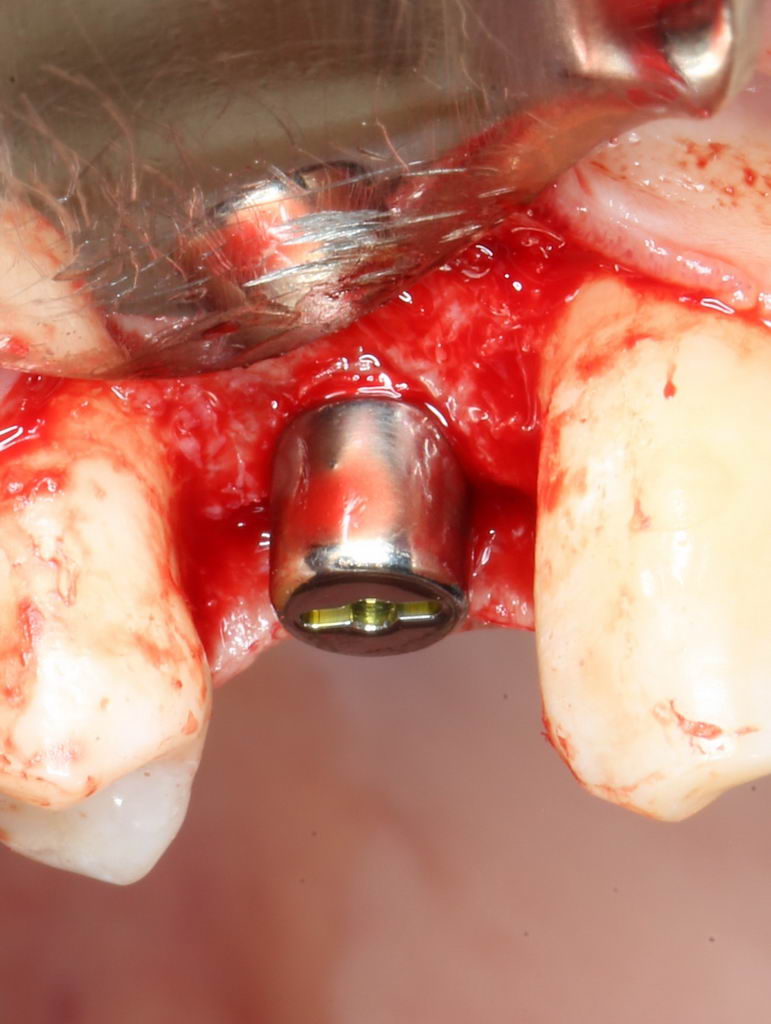

Больше нам абатмент TempBase не нужен, мы его убираем:

Без абатмента можно оценить позиционирование имплантата по глубине погружения. Напомню, что XiVE — это субгингивальная имплантационная система, поэтому ортопедическая платформа имплантата должна находиться на уровне костной ткани. Что и было выполнено в нашем случае.

И, коль всё в порядке, переходим к следующему этапу операции — установке формирователя десны.